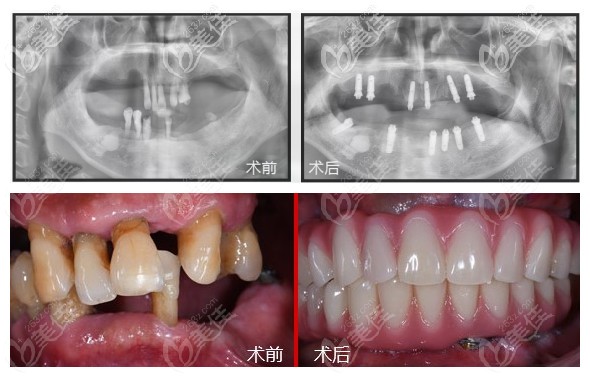

全口allon6種植牙前后對(duì)比圖↓↓↓

郭老種牙后反饋:"手術(shù)感覺(jué)還好,30分鐘就弄給弄好一口牙,現(xiàn)在有牙就系唔一樣,嘴巴不再凹陷,我都變靚仔好多了。"